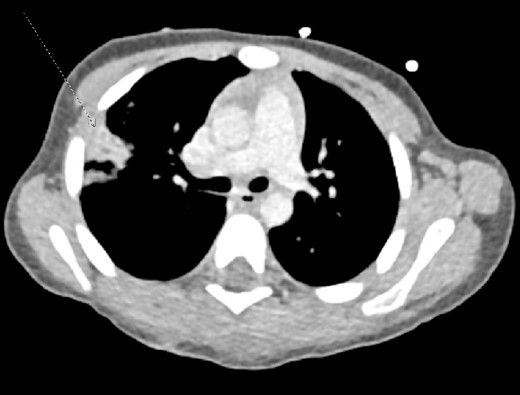

During the secondary survey of the patient, he was found to be in sinus tachycardia, with three lacerations to the scalp closed with suture and staples, and an inferior neck wound with surrounding erythema and clear drainage. Multiple wounds on his back were closed with sutures, and tender to palpation with ecchymosis (Fig. 1). Also, three wounds to his bilateral buttock. Initial labs showed lactic acidosis and leukocytosis. He was started on Vancomycin, Rocephin, and intravenous fluids. CT imaging of the head showed an acute penetrating injury at three sites, with left parietal and occipital scalp laceration and associated depressed comminuted calvarial fractures with trace pneumocephalus, along with a right lung pulmonary contusion and penetrating left buttock wound (Figs 2 and 3). He was transferred to a pediatric trauma center with an established PICU and pediatric neurosurgery for further care and treatment. It was elected to proceed with the least invasive option to oversew the leaking wound at the bedside and a lumbar puncture was obtained to evaluate for possible meningitis. The patient ultimately received tetanus prophylaxis and treatment as well as an empiric course of antibiotics directed against meningitis and was discharged to home with his mother with outpatient follow-up.

Intravenous contrast computed tomography of chest, abdomen, and pelvis showing right upper lobe pulmonary contusion/laceration. No pneumothorax or pleural effusion.